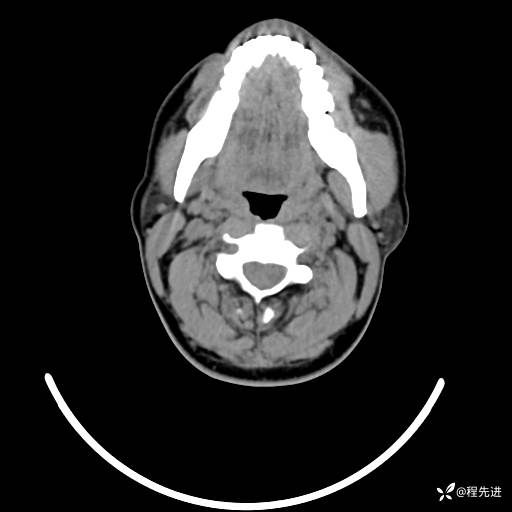

CT平扫+增强: